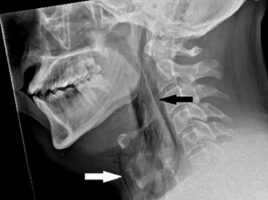

Ένας άνδρας γύρω στα 30 από το Ηνωμένο Βασίλειο μετέβη στα επείγοντα με έντονο πόνο και πρήξιμο στον λαιμό, που δυσκολευόταν να κινήσει. Όπως εξήγησε στους γιατρούς, ο πόνος εμφανίστηκε ξαφνικά όταν επιχείρησε να «πνίξει» ένα φτέρνισμα, κρατώντας τη μύτη του κλειστή και το στόμα του κλειστό ταυτόχρονα. Ο άνδρας οδηγούσε και υπέφερε από συμπτώματα […]